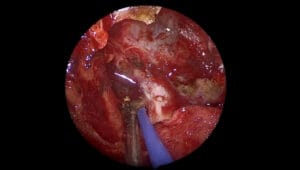

El Dr. Patel utiliza una técnica innovadora que emplea fresado subacuático, un procedimiento menos invasivo y más preciso en comparación con las técnicas tradicionales. Este enfoque implica el uso de una fresa de diamante de alta velocidad y agua para minimizar el calor generado durante el fresado, lo que reduce el riesgo de daño a los tejidos circundantes y mejora la seguridad del procedimiento.

La intervención comienza con una incisión estándar para acceder al oído medio. Luego, se emplea el fresado subacuático para liberar el martillo fijado, utilizando una serie de fresas de diferentes tamaños para liberar la fijación ósea sin comprometer la cadena osicular. Durante el proceso, se tiene especial cuidado para no dañar la cuerda del tímpano, una estructura delicada que podría causar pérdida auditiva sensorineural si se ve afectada.